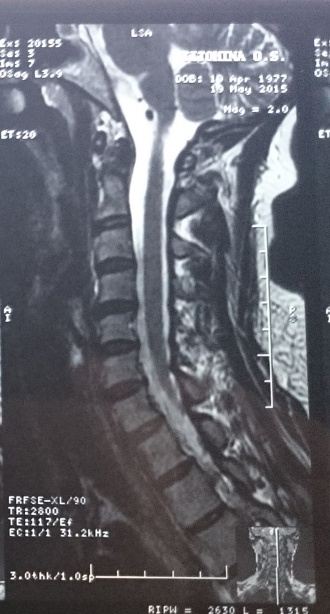

• Снимок №1: май 2014 года

• Снимок №2: май 2015 года

На МРТ можно увидеть классическую картину повреждения шейного отдела. На левом снимке (№1 - май 2014 года) отчетливо видны характерные признаки «хлыстовой» травмы позвоночника. Во-первых, это выпрямление шейного лордоза — так называемый «симптом струны»: шейный отдел должен плавно прогибаться, формируя лордоз, на снимке же он выглядит прямым, как натянутая струна. В одном месте позвонки «выгибаются» в обратную сторону — наблюдается посттравматический кифоз. Во-вторых, между всеми позвонками — от второго до пятого — можно видеть протрузии и грыжи. Особенно выдается грыжа между 4 и 5 позвонками: на снимке видно, что в этой области есть компрессия спинного мозга.

На правом снимке (№2 - май 2015 года) грыжи и протрузии значительно уменьшились. Ушло воздействие на спинной мозг — основная угроза, которая в данном случае являлась показанием к операции.

Этим можно объяснить исчезновение неврологических симптомов у пациентки: нарушения речи, головных болей и головокружений. Я считаю, что девушка на правильном пути: необходимости в хирургическом вмешательстве действительно нет, можно продолжать заниматься и улучшать состояние здоровье от занятия к занятию.